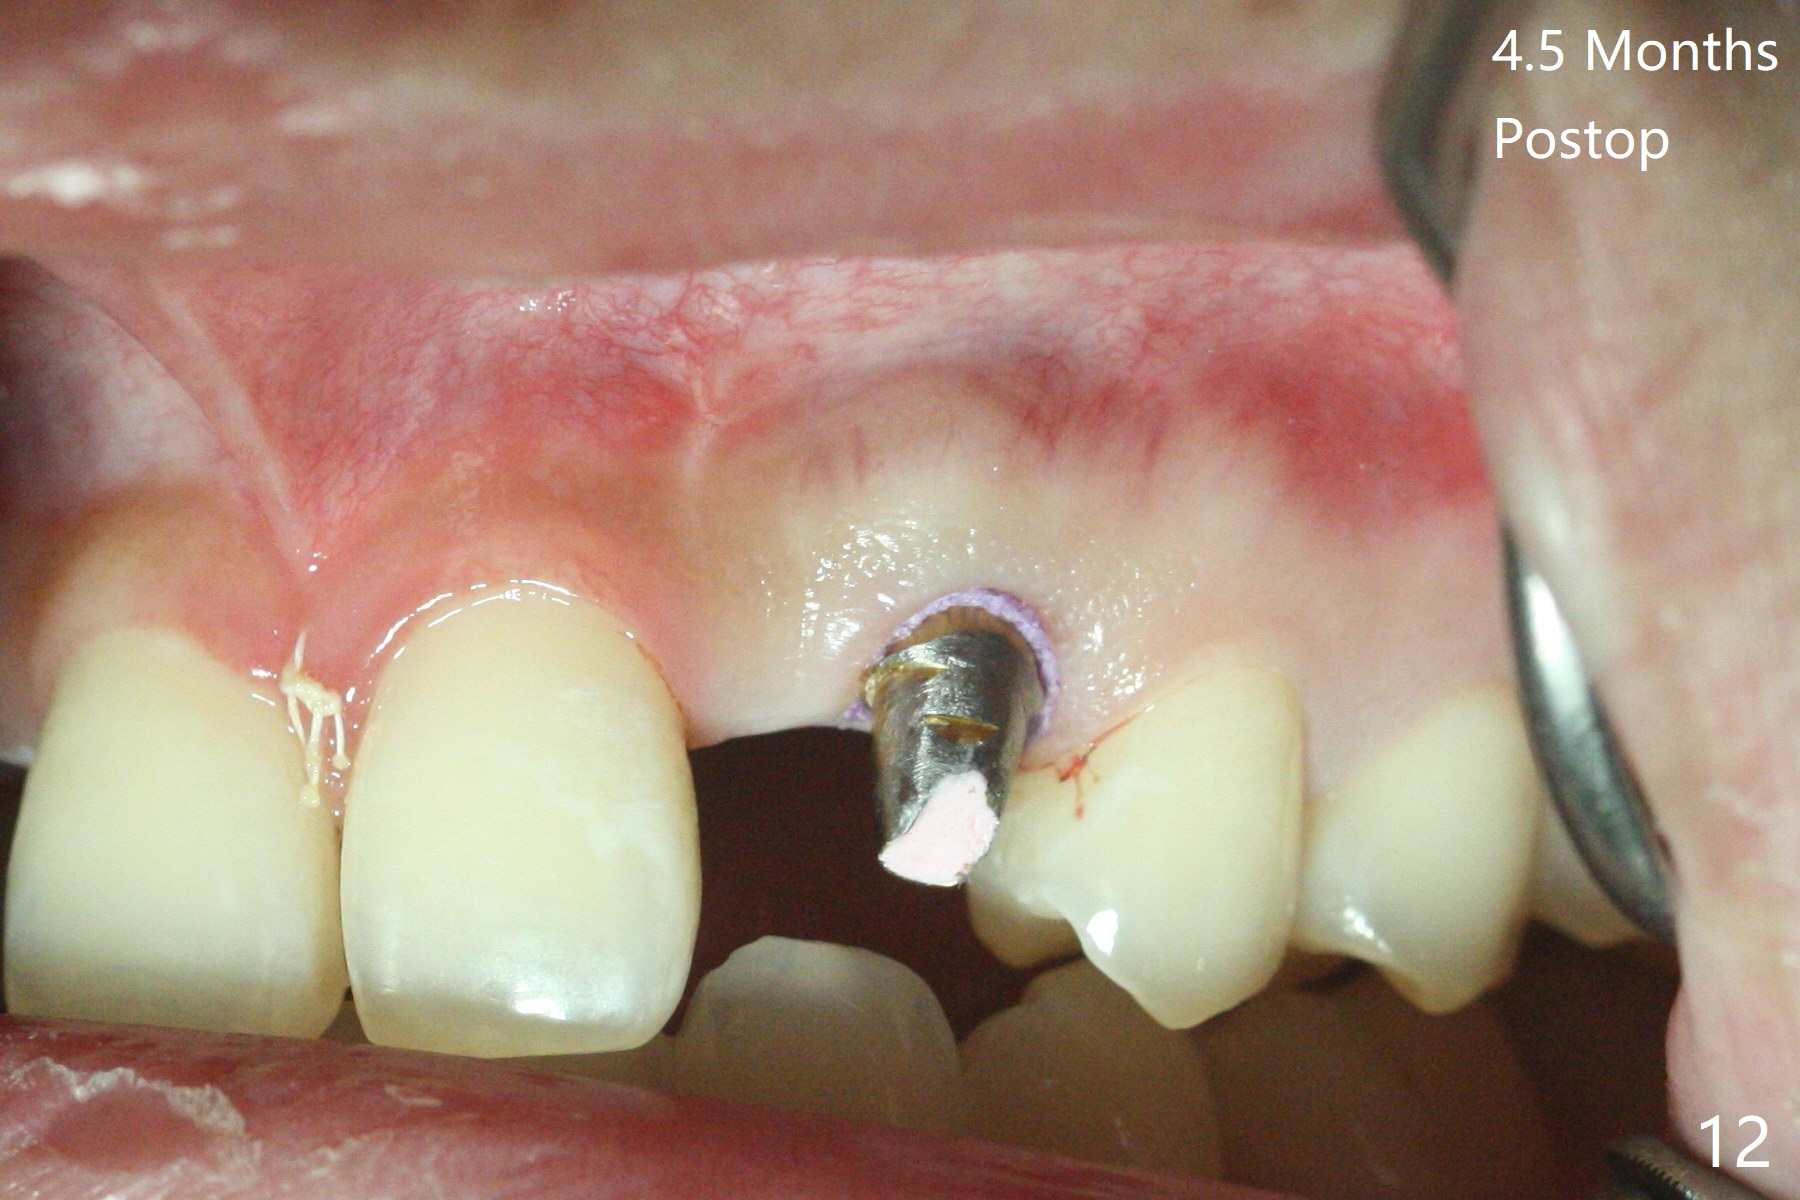

18岁男从外州大学回来,无症状,但是6号牙(右上尖牙)颊侧瘘道(图一,二(角化龈充分(箭头))),根尖片显示植体近中骨吸收(图三:*),而对侧植体仿佛骨整合(图四)。患侧切开后发现植体颊侧暴露,松动。拔除后骨缺损由粘性骨粉修复(图七,九:*),覆盖PRF膜(图七:P)和带钛网(图九:^)不可吸收膜(图五-七),后者用两个小钉子固定(图六(腭侧),七(颊侧),九),使用新的刀片和一个特殊尖头剥离器在颊侧骨膜下相当广泛分离,使用PTFE缝线,粘膜下水平褥式缝合之后(图八:箭头),多个垂直间断缝合,两个乳头垂直褥式缝合。术后一周伤口没有裂开,术后疼痛肿胀已经消退(图十)。术后十八天牙槽嵴仿佛比对侧还要宽(图十一,三与图十二,四(取模)对比)。术后5.5个月伤口没有裂开,牙槽骨,角化龈宽(图十六),与钛网和两个小钉子固定有关(图十五,十七)。CT显示牙槽骨只能容纳2.5或者3.0毫米植体(图十八)。11号牙植体牙冠粘固后没有骨质吸收(图十九),其实10,11号牙颊侧骨板隆起(图二十至二十二),而6植体失败,颊侧骨板吸收,甚至累及5号牙(图十七)。